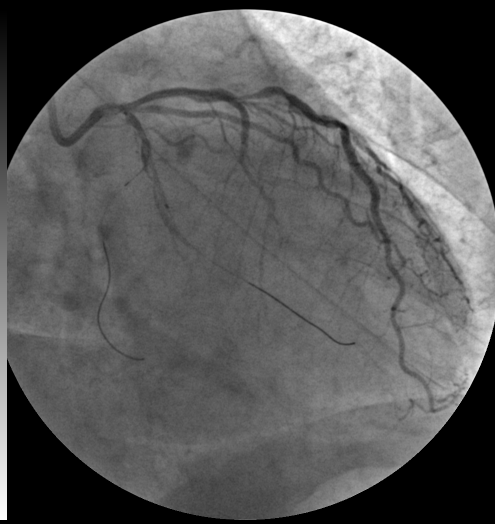

图1. 箭头所示左冠状动脉回旋支(cx)近端长段闭塞,长度17mm

图1 手术直播冠脉造影检查,白色箭头为左回旋支闭塞血管介入处理

造影显示患者的冠状动脉回旋支近段完全闭塞(翻拍照片)

造影见回旋支近段闭塞.